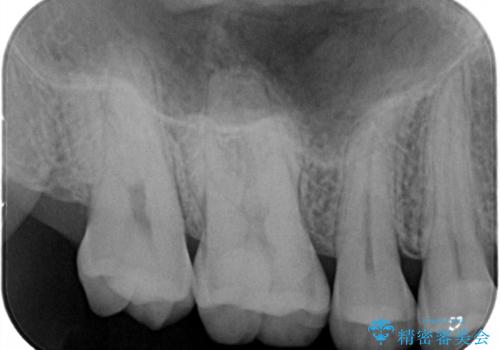

今回は虫歯が大きかったものの、ぎりぎり神経に達しておらず、セラミックインレー(つめもの)の治療のみで完了しました。初診時に虫歯を除去し、後日神経のテストをして正常反応を確認しました。

虫歯を徹底的に除去し、なおかつ神経に達しているかを慎重に判断するには、どうしても顕微鏡&長時間の診療が必要になりますが、保険外治療となります。

自分の歯や神経をなるべく残すには保険外治療をおすすめしています。